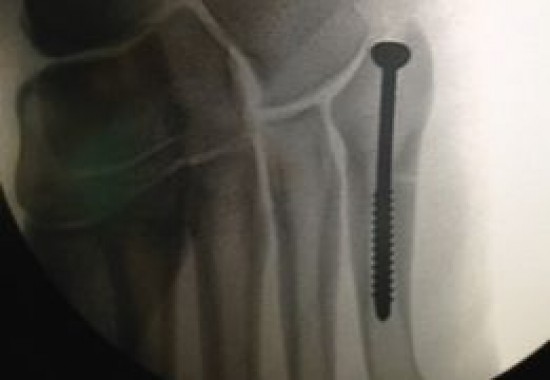

La intervención quirúrjica ‘se trata de un procedimiento habitual en la osteosíntesis, un tratamiento quirúrgico usado en fracturas y cuya intervención dura escasos 30 minutos’, anunció el medio AS en la web.

‘El objetivo de esta práctica es reducir y fijar de forma estable la rotura. Para ello es necesario la implantación de dispositivos de placas, tornillos, o como en este caso, un clavo’, culminó el medio español.